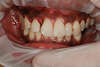

La survenue d'une infection des gencives a provoqué le déplacement de certaines dents qui sont mobiles. La gencive est gonflée et saigne facilement.

Après réalisation d'une thérapeutique anti infectieuse adaptée, un traitement orthodontique a permis de retrouver un sourire harmonieux et des dents solides.